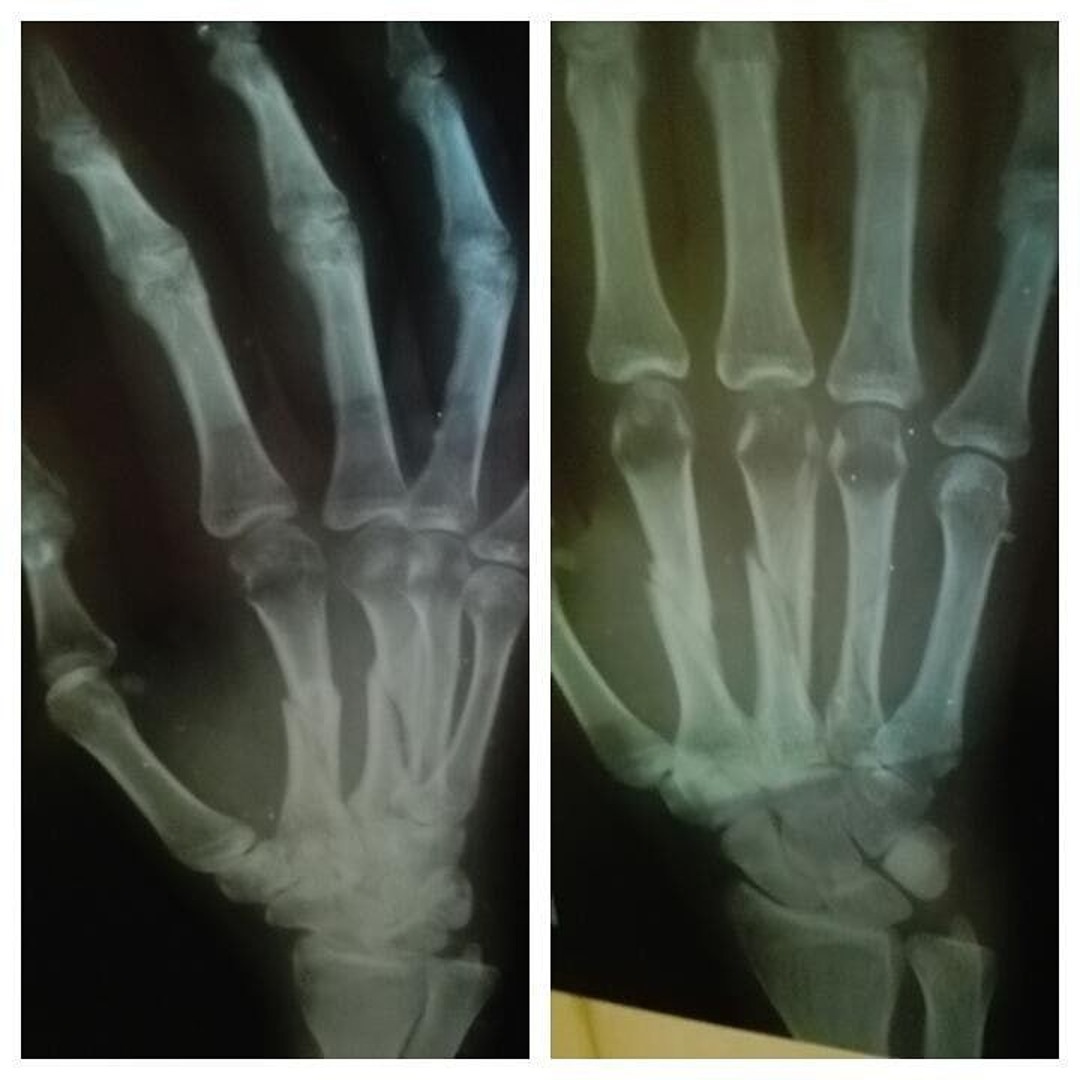

Перелом Полулунной Кости Кисти Руки Фото

Перелом Полулунной Кости Кисти Руки Фото 114 фото